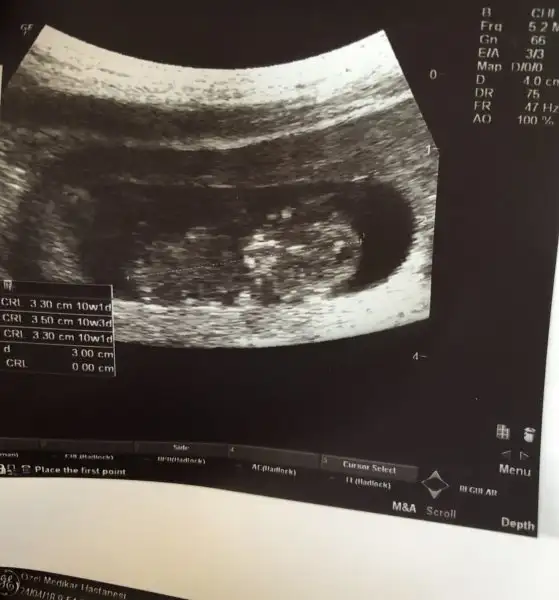

Yk canım kordon değil nub olduğu kesin .ama çok dik olmadığı için doktor kız dedi ben doktora erkek dedim:) 45 ° acıyla dik olunca erkek deriz dedi bende peki dedim.acı tahmini yaptım ben 40larda bakalım ne çıkacak

12 haftalık canım bu ultrason da pazartesi 14 hafta tekrar gideceğim bakalım .bebikim ne alemde bende merak ediyorum gerçekten asla cinsiyet ayrımı yaptığım için değil haklı cıkacakmıyım bakacagız.bak açıyı çizdim bu açı 40° de :)